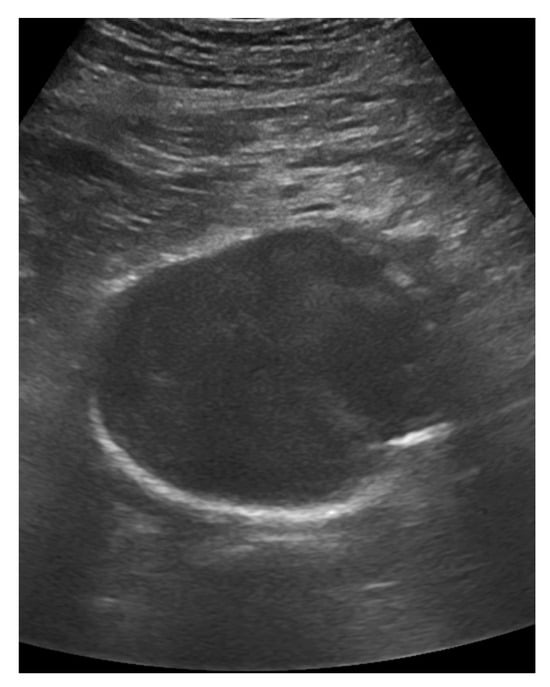

7.4.1. Abdominal Aortic Aneurysm

An examination of the abdominal aorta can be performed with either a convex or sector probe []. The aorta is assessed for dilation with the ultrasound transducer in a transverse orientation. Traditionally, the diameter is measured in the anterior–posterior orientation, but saccular aneurysms should not be overlooked. A diameter of over 3 cm is considered to be an aortic aneurysm. A diameter of over 5 cm increases the risk for rupture (Figure 18). The most important risk factor for rupture is the diameter []. There is no measurement that proves a rupture, but for women with a diameter of more than 5 cm and for men with a diameter of more than 5,5 cm, the rupture risk increases, and, therefore, certain guidelines see this as an indication for surgery even if patients are asymptomatic. Any symptomatic aneurysm should be operated on []. Thus, in the event of shock and the presence of an aortic aneurysm without any other cause for shock, a ruptured aortic aneurysm must be considered. Hemorrhage is often retroperitoneal, rather than intraperitoneal, where it is difficult to identify. Possible additional signs in abdominal aortic aneurysm are summarized in the following sequence.

Figure 18.

A large aortic aneurysm of 6.3 cm diameter.